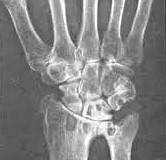

Склероз коленного сустава

Выявляется при развитии состояния остеоаротроза колен. Больные жалуются на боли в коленях при физической нагрузке, а затем и в покое, хруст при движении, постепенное уменьшение амплитуды, деформацию коленей и нижних конечностей.

Частым следствием субхондрального склероза коленных суставов является развитие варусной или вальгусной деформации (О- и Х-образные ноги).